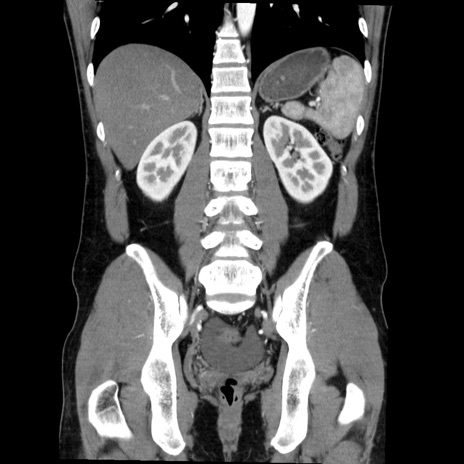

症例36(冠状断像)

【症例】20歳代 男性

【主訴】心窩部痛

【現病歴】今朝より上腹部痛あり。一旦軽快していたが再度出現したため救急要請。昨日夕に白身の魚を含む刺身を食べた。

【身体所見】BP 136/89mmHg、HR 74/min、BT 37.0℃、腹部:膨満、軟、心窩部に圧痛あり。反跳痛なし、筋性防御なし、腸雑音やや亢進あり。

【データ】WBC 17700、CRP 0.48